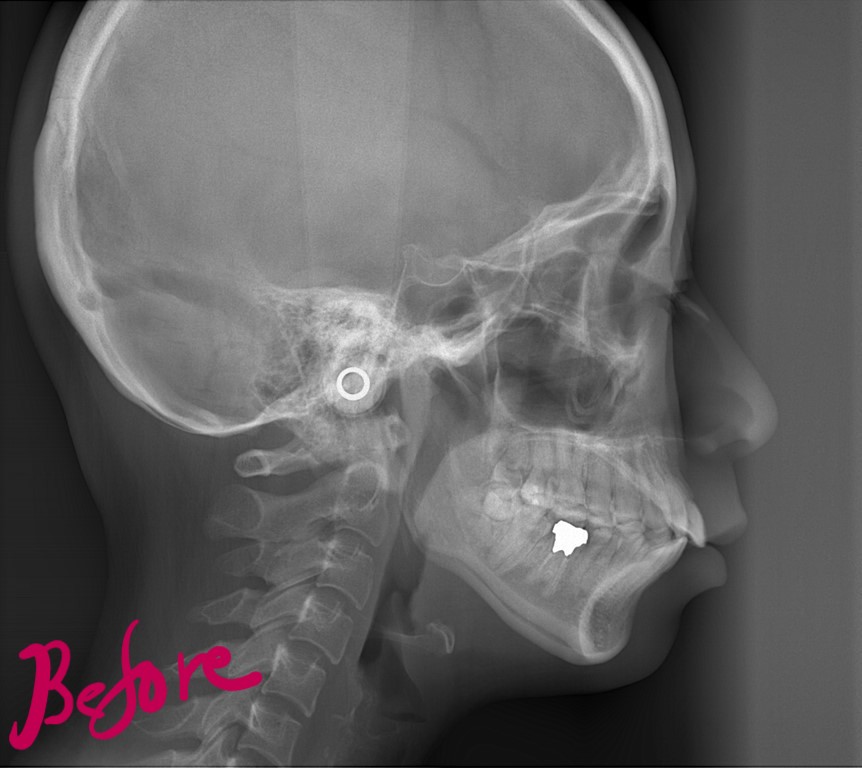

レントゲン写真でも比較してみましょう

左側が矯正治療前、右側が矯正治療後